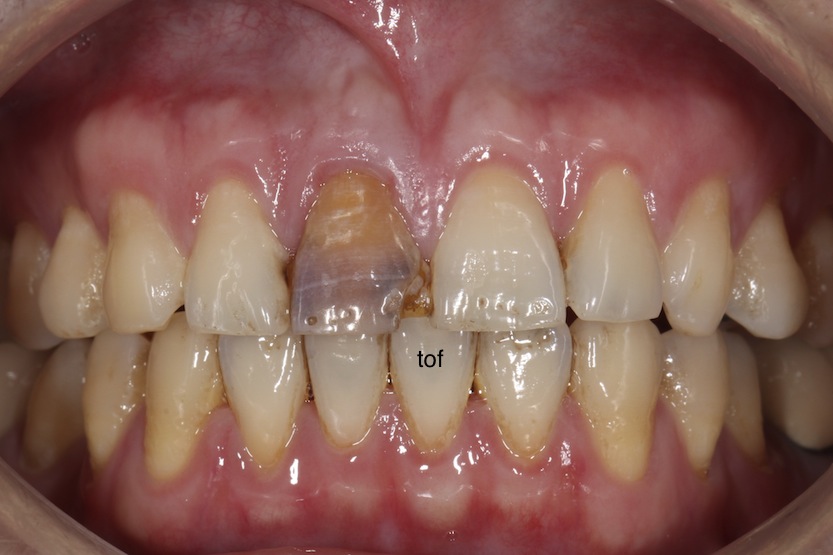

經過 root canal treatment,上了牙根柱,做上臨時假牙。

以這個案例來評分 前牙美學 的分數好了:

牙齦健康:我們可以看到,相較其他牙齒,雖然 #11 的牙齦沒有發炎的特別嚴重,但看起來也不是完全健康,所以8分內只得4分。

齒頸部牙齦顏色:這是最常被看出是不是假牙的部份,跟#21比起來,#11 的確在 free gingiva margin 的部份顯得比較黯淡,所以8分內只得4分。

齒間乳突:以這個案例來說,齒間乳突大致上都還在,所以單項部分得到滿分8分。有人會說,那如果這顆牙齒間乳突很完整,其他部分有 black triangle 怎麼評分?答案是還是一樣評分,因為我們評估的是整體的感覺,如果其他部分有 black triangle,這個照片的美觀還是會不好。

牙齦線分布:完美的牙齦線希望是由單側由犬齒到中門齒,希望是 high low high,以這個 case 來說,並沒有達到理想,就算醫師建議客戶做,客戶也不會做,所以會被扣分,4分只得到2分。

牙齦 zenith 及對稱性:gingival zenith 就是單顆牙牙齦的最高點,通常是在中線偏 distal,以這個案例來說,大致符合,可以得到4分中的4分。

口腔衛生:口腔衛生,病人有責任,牙醫師也有責任,以這個案例來說,在鄰近牙面上,還是有 plaque,所以6分中只得3分。

牙齒型態:這個案例成功的複製了 #21 整個外型形狀,模仿的維妙維肖,所以得滿分8分。

牙齒尺寸/比例:牙齒寬/長比應該是大約0.8,所以這個案例大致符合,8分得8分。

牙齒長軸:牙齒長軸自犬齒到中門齒,是越來越垂直,這個案例大致符合,8分得8分。

牙齒臨接點位置/切端角:請參考 Pascal Magne 所著 Bonded Porcelain Restorations 這本書第 64頁,及 Mauro Fradeani 所著 Esthetic Rehabilitation in Fixed Prosthodontics, Volume 1, P. 188-189。以這個案例來說,還算符合 contact 越 distal 越 apical,所以4分得4分。

有關牙齒顏色的 value, chroma, hue, translucency:這四項,因為蘇湖醫師及技師都有研讀 tof 部落格的各篇文章,所以都是滿分,總共得到 20分。

牙齒表面結構:當然是滿分,6分。這位技師注重細節,一級棒。

切端線型態:理想中的 high low high,嗯,沒有做出來,病人也不會願意做,好吧,0分。

牙齒排列對稱性:ok,是對稱的,尤其是中門齒,對稱很重要,4分得4分。

所以蘇湖醫師的這個案例,雖然是單顆牙,但也拿到了總分 79分,尤其單顆牙,客戶來本來就是只要做那顆牙,醫師能夠做的不多,也不會聽你說要改其他牙牙齦高度等等的,所以能到 80 分就很 ok了,除非病人本來的牙齒就很美….. 各位看倌,可以拿你自己的案例來看看哦!